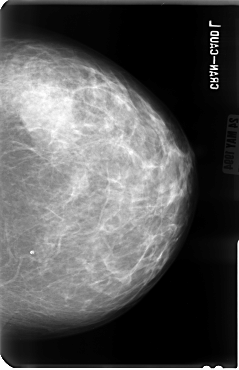

B_3040_1.LEFT_MLO

LEFT_MLO LINES 4808 PIXELS_PER_LINE 3096 BITS_PER_PIXEL 12 RESOLUTION 50 NON_OVERLAY